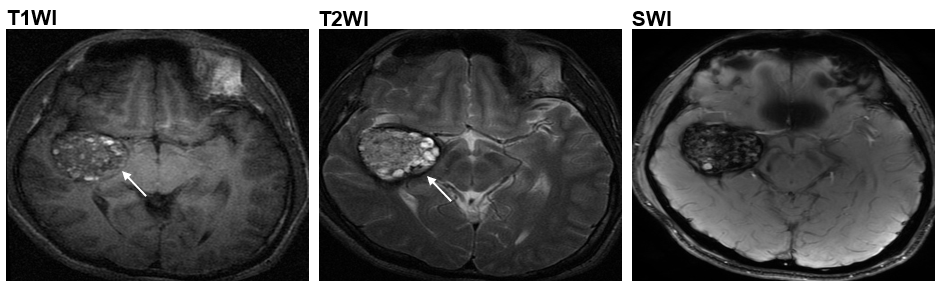

Now, using next-generation sequencing and computational approach, a research team led by Prof. WANG Jiguang, Assistant Professor from HKUST’s Division of Life Science and Department of Chemical and Biological Engineering, in collaboration with Prof. CAO Yong from the Beijing Tiantan Hospital, analyzed the genomic data of 113 CCM patients and identified another mutation called MAP3K3 c.1323C>G, which is found to be responsible for almost all the tested cases who developed popcorn-like lesions in their brain arteries - the most common one among the four types of CCM lesions1(type II CCM).

At present, magnetic resonance imaging (MRI) is a commonly used non-intrusive means that doctors can base upon for diagnosis and treatment. However, the MRI images can only tell the size and type of the lesions, but not the gene responsible for the problem – which can only be ascertained by surgery and laboratory tests. Now, the HKUST research team designed a computational method that could help assess the probability of connection between the lesion shown in the MRI image to the genetic mutation MAP3K3 c.1323C>G. So CCM patients with this gene mutation may be able to receive more targeted treatment without having to undergo surgery – which could bear serious risks including cerebral hemorrhage or new focal neurological deficits.